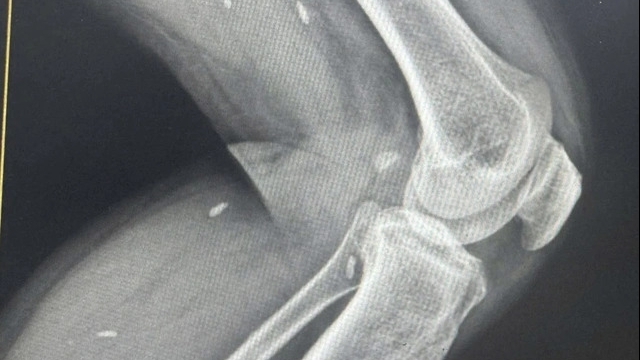

| Bệnh nhân có vết thương thấu từ cực giữa đến rốn thận, thận không có khả năng phục hồi nên bác sĩ phải cắt thận để cầm máu. Ảnh: BVCC |